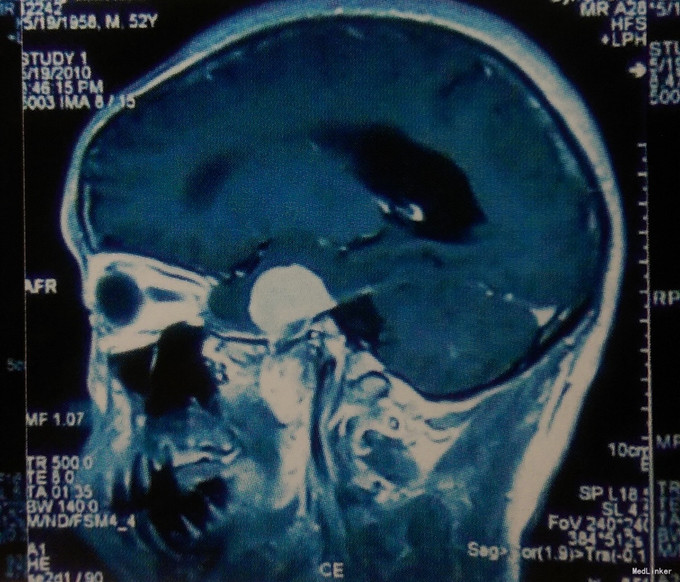

入院查体:体温37℃,脉搏80/min,呼吸20/min,血压110/80mmHg。神志清楚,言语清晰,语言流利,应答切题,查体合作,双瞳等大等圆,直径3.0mm,对光反应灵敏,双眼球各向活动充分。余查体未见异常。GCS评分15分,KPS评分100分。 术前影像学检查 头颅MRI:左侧鞍旁可见一类圆形肿瘤,肿瘤形状规则,强化均一,与左侧中颅窝底及左侧海绵窦硬膜关系密切,可见“鼠尾”征,考虑左侧鞍旁脑膜瘤。